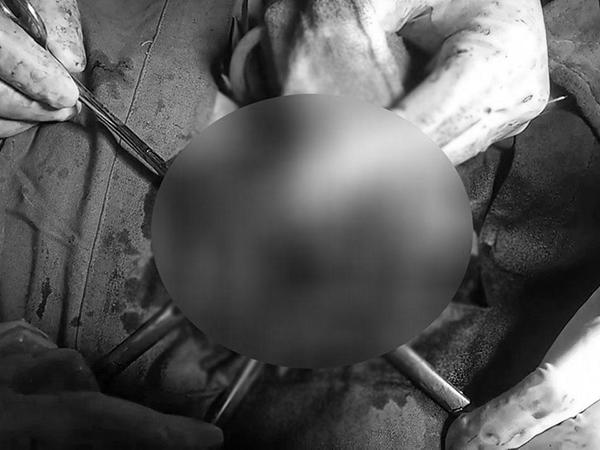

Các bác sĩ tiến hành siêu âm để xác định vị trí chính xác của đoạn dương vật bị gãy, được định vị bởi một cục máu đông và sự tích tụ nước tiểu trong mô dương vật. Sau đó, bệnh nhân được giới thiệu đến một chuyên gia tiết niệu để phẫu thuật.

Bệnh nhân lập tức được các bác sĩ phẫu thuật chữa "gãy súng".